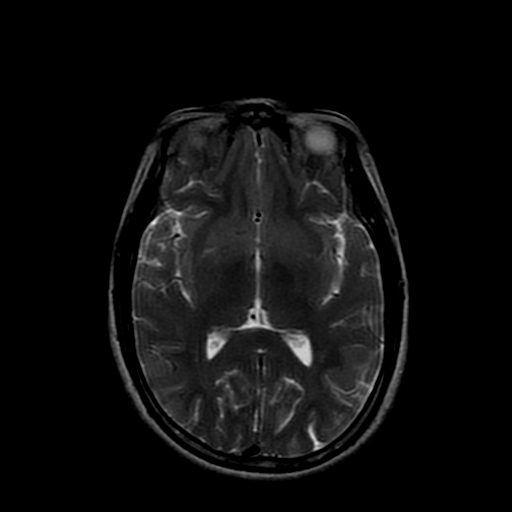

女性,47岁。mri号03027,外伤致头痛9天,抽搐一天,原无类似病史。

双侧海马的信号都有异常。

双侧海马硬化!

颞叶前部萎缩,海马萎缩,t2wi海马高信号,支持海马硬化。

双侧海马硬化.

双侧海马区t1低,t2高信号。为什么都考虑硬化?发病原因?鉴别诊断:炎症,梗塞等能一下子除外吗?